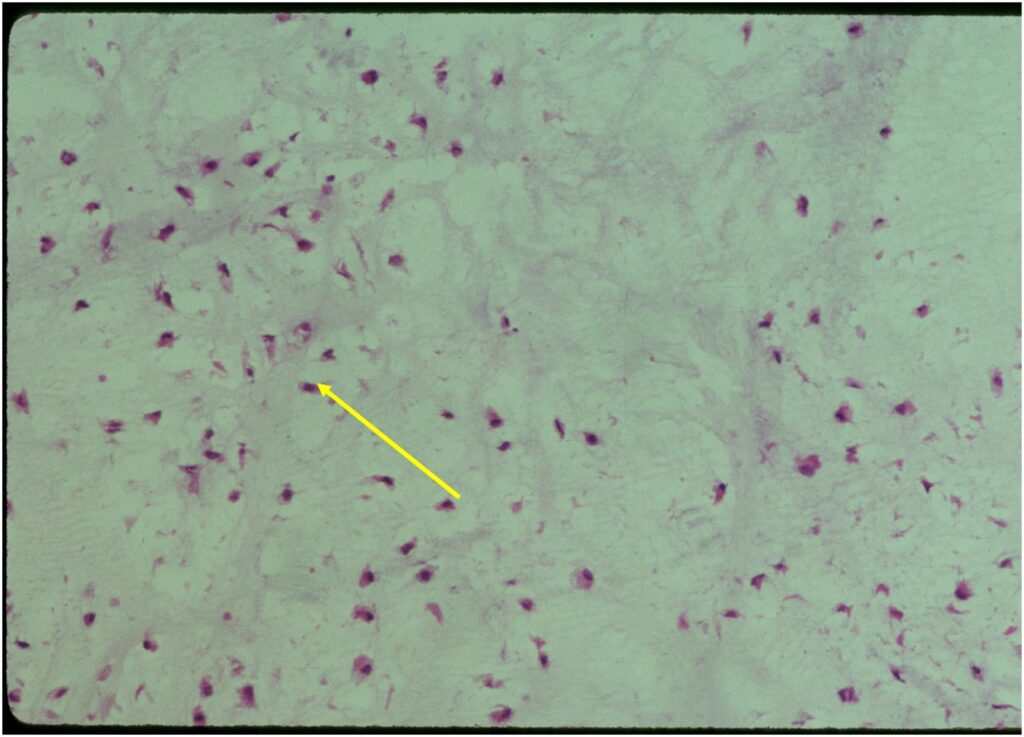

Pathology

- Rests of hyaline cartilage with a lobular growth pattern

- Cells are within lacunae

- Hypocellular with cells spaced apart separated by matrix

- Cells have small nuclei and are similar size and shape (no pleomorphism)

- No mitotic figures

- The matrix has a ground glass basophilic appearance

- The matrix contains glycosaminoglycans that attract fluid/water and gives it a bsophilic appearance and show as high signal intensity on T2 weighted MRI

- The collagen of the matrix is organized in a manner such that the refractile index under a microscope gives a ground glass appearance to the matrix. One can not visualize the actual collagen fibers.

Microscopic Pathology

- Enchondromas are well defined lesions with cartilage arranged in lobules that are separated by fibrovascular septa

- Enchondral ossification may occur around periphery of lobules and when calcified appear as “Rings and Arcs” on X-rays

- Cells are in lacunae and have small dark nuclei

- Low cell count, cells appear bland with few chondrocytes and are similar size and shape

- Although some enchondromas may have areas that are hypercellular and may have two or three cells within a lacunae

- No entrapment or destruction of trabeculae

- There should be no myxoid change in long bone lesions (there is occasional myxoid change in enchondromas of the digits)